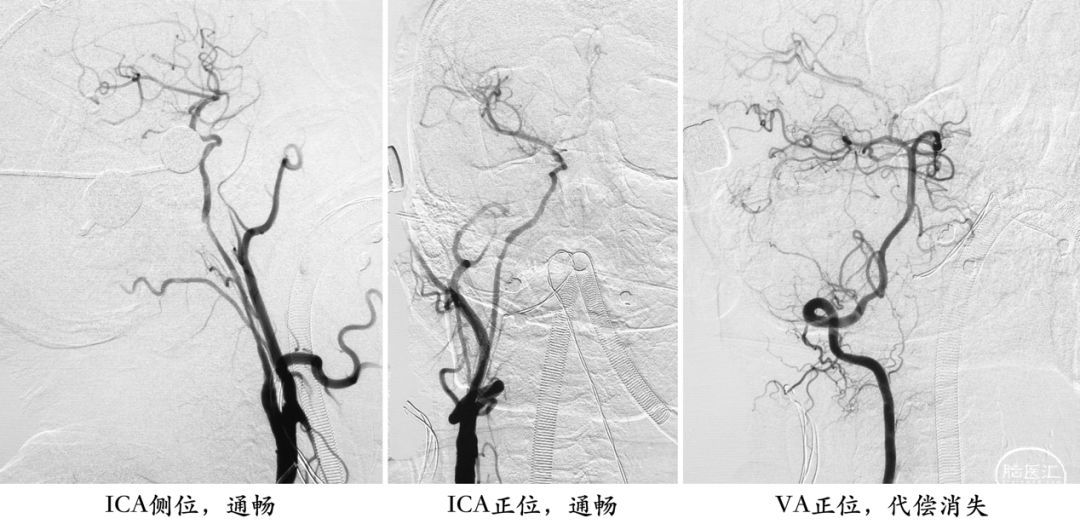

对于超声的结果,我有些迟疑是否要进行急诊手术。再次复查DSA,结果真的是那样一支小动脉啊![]() ,从椎动脉肌支吻合到这个分支,向下进入ICA起始段不远处,再逆行向上供应整个ICA。

切除斑块后,血管自然是通畅了,VA的肌支代偿也没有了。